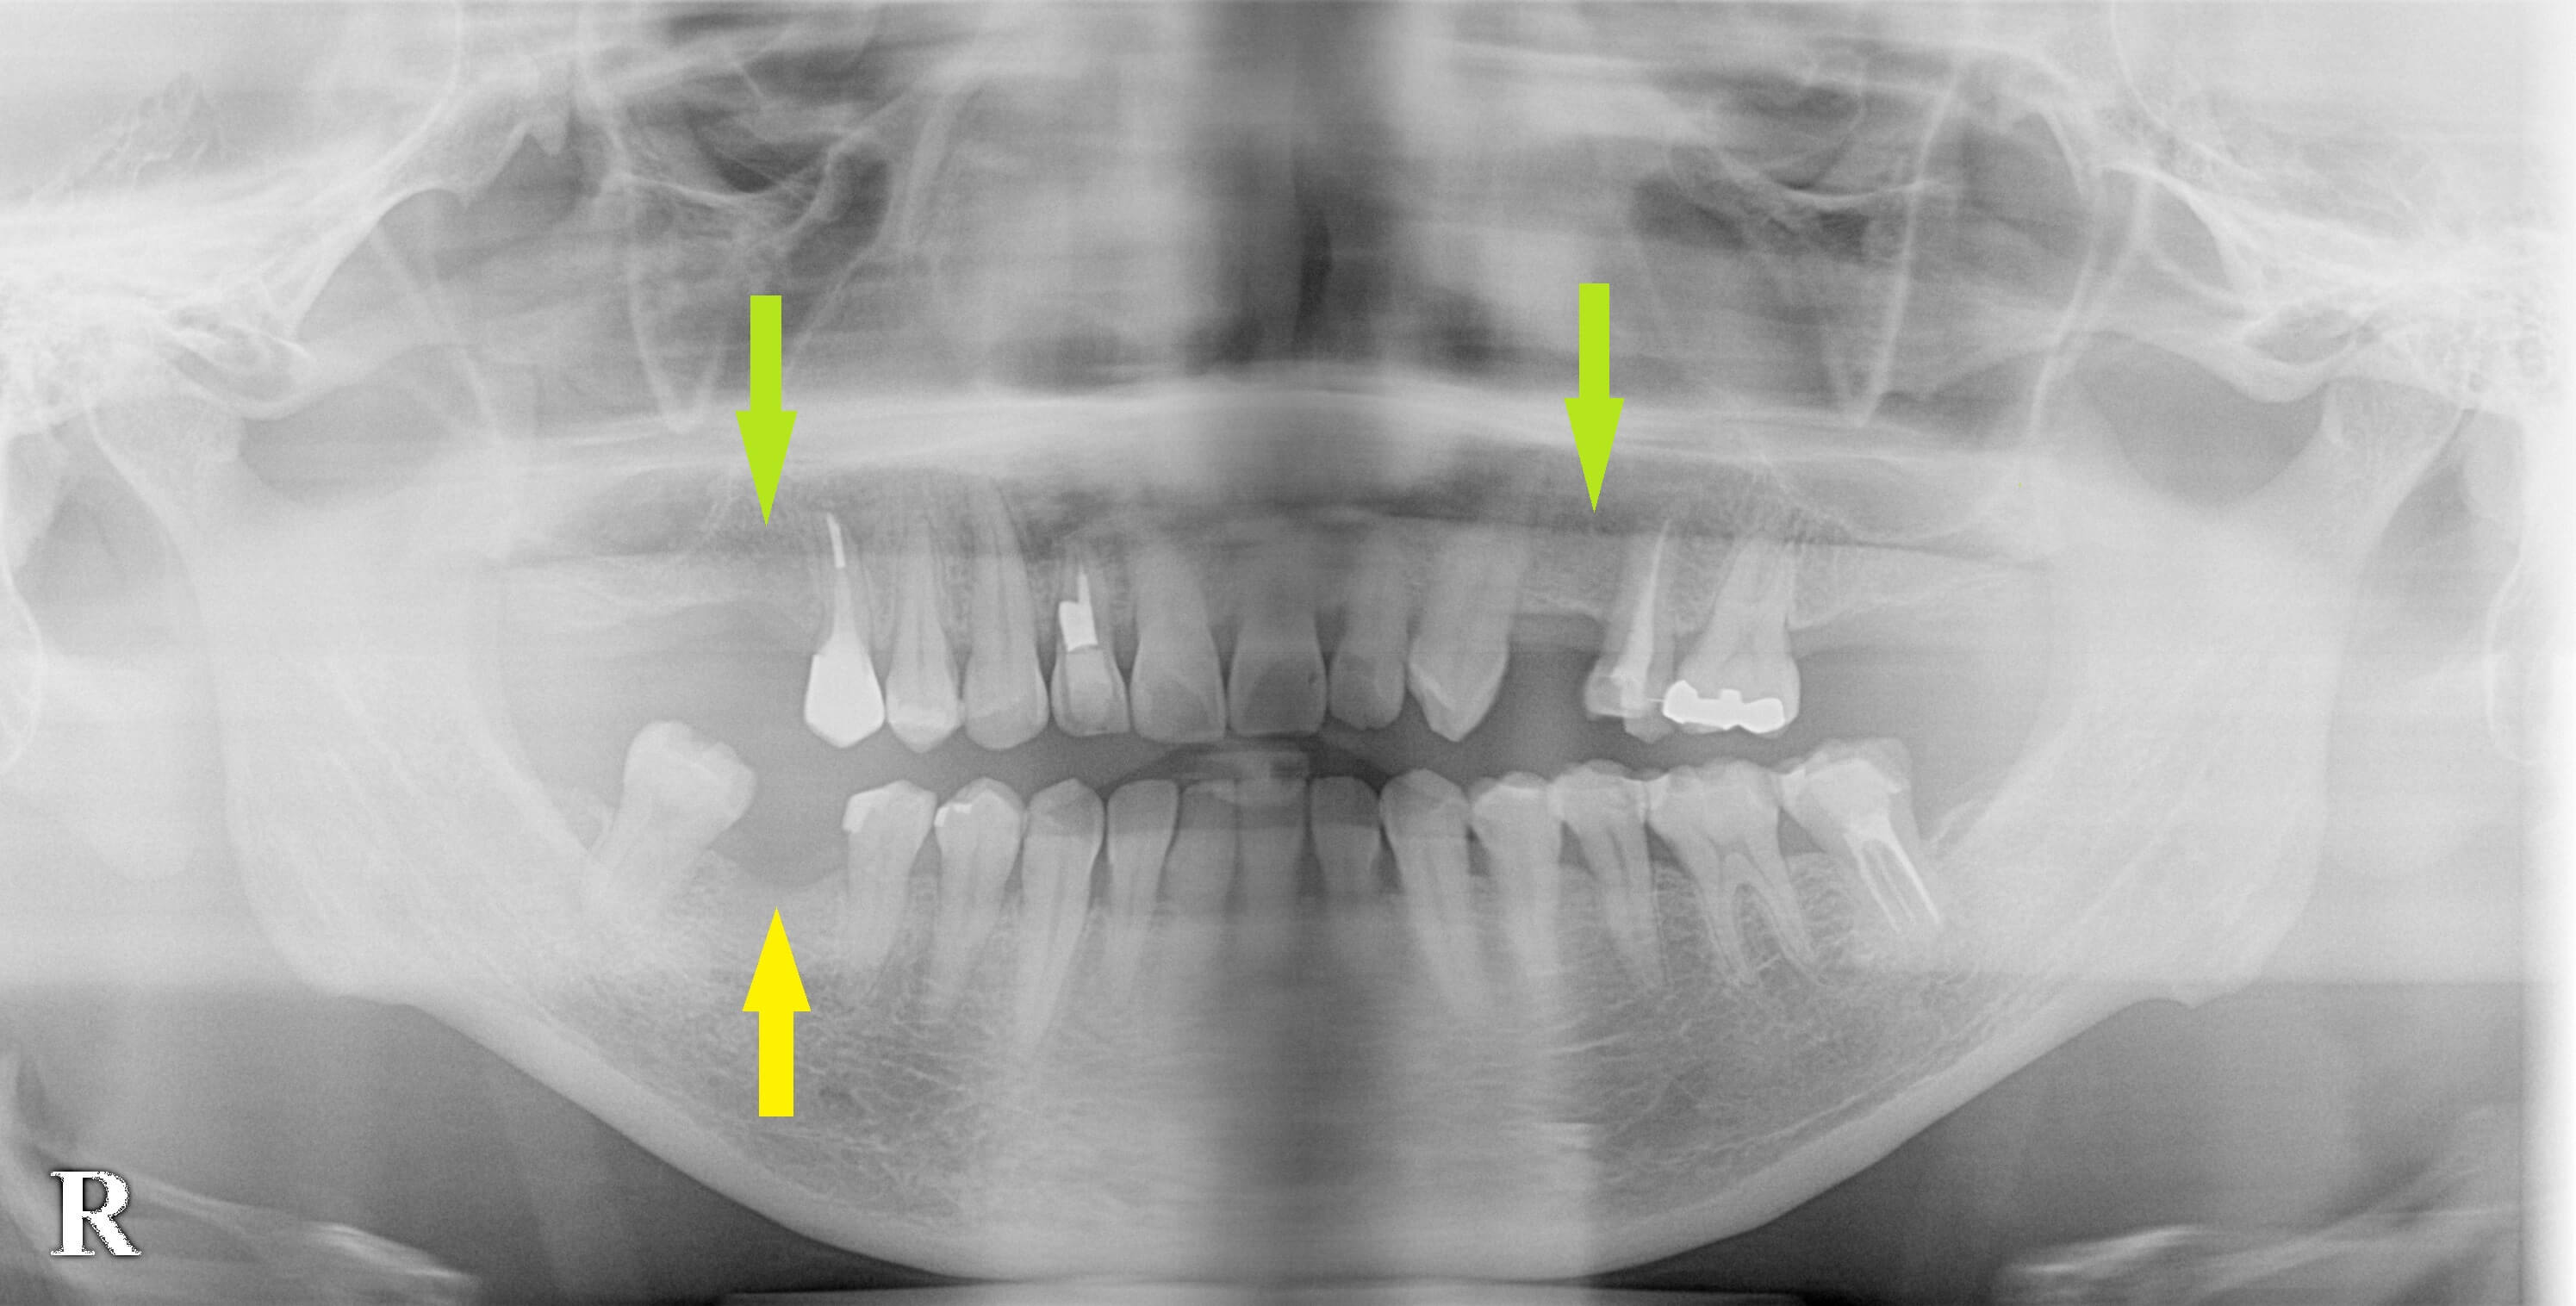

何本か歯が抜けているのですが、今回は右下顎の第一大臼歯のみの、インプラント治療を希望されて来院されました。

CTにて骨量は問題ありませんでしたので、本日インプラント埋入術を行いました。

この歯の治療が上手くいったら、右上顎の第一大臼歯と左上顎の第一小臼歯も考えたいとのことでした。